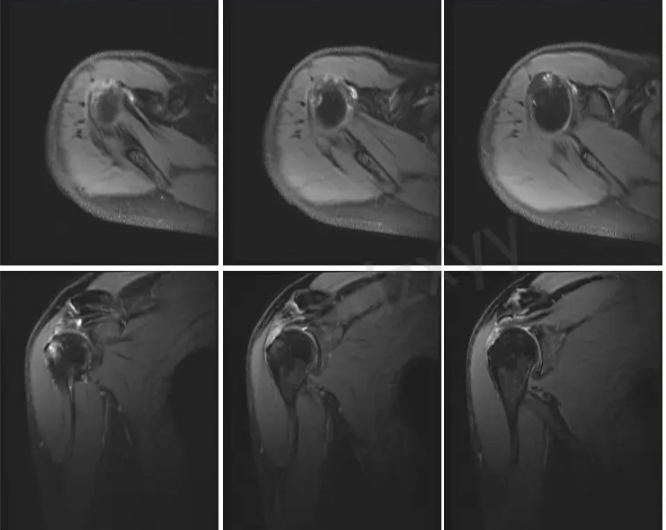

3.核磁共振成像(MRI)是肩袖损伤的重要检查手段,它能清晰准确的显示肩袖肌腱的形态、结构和损伤程度。